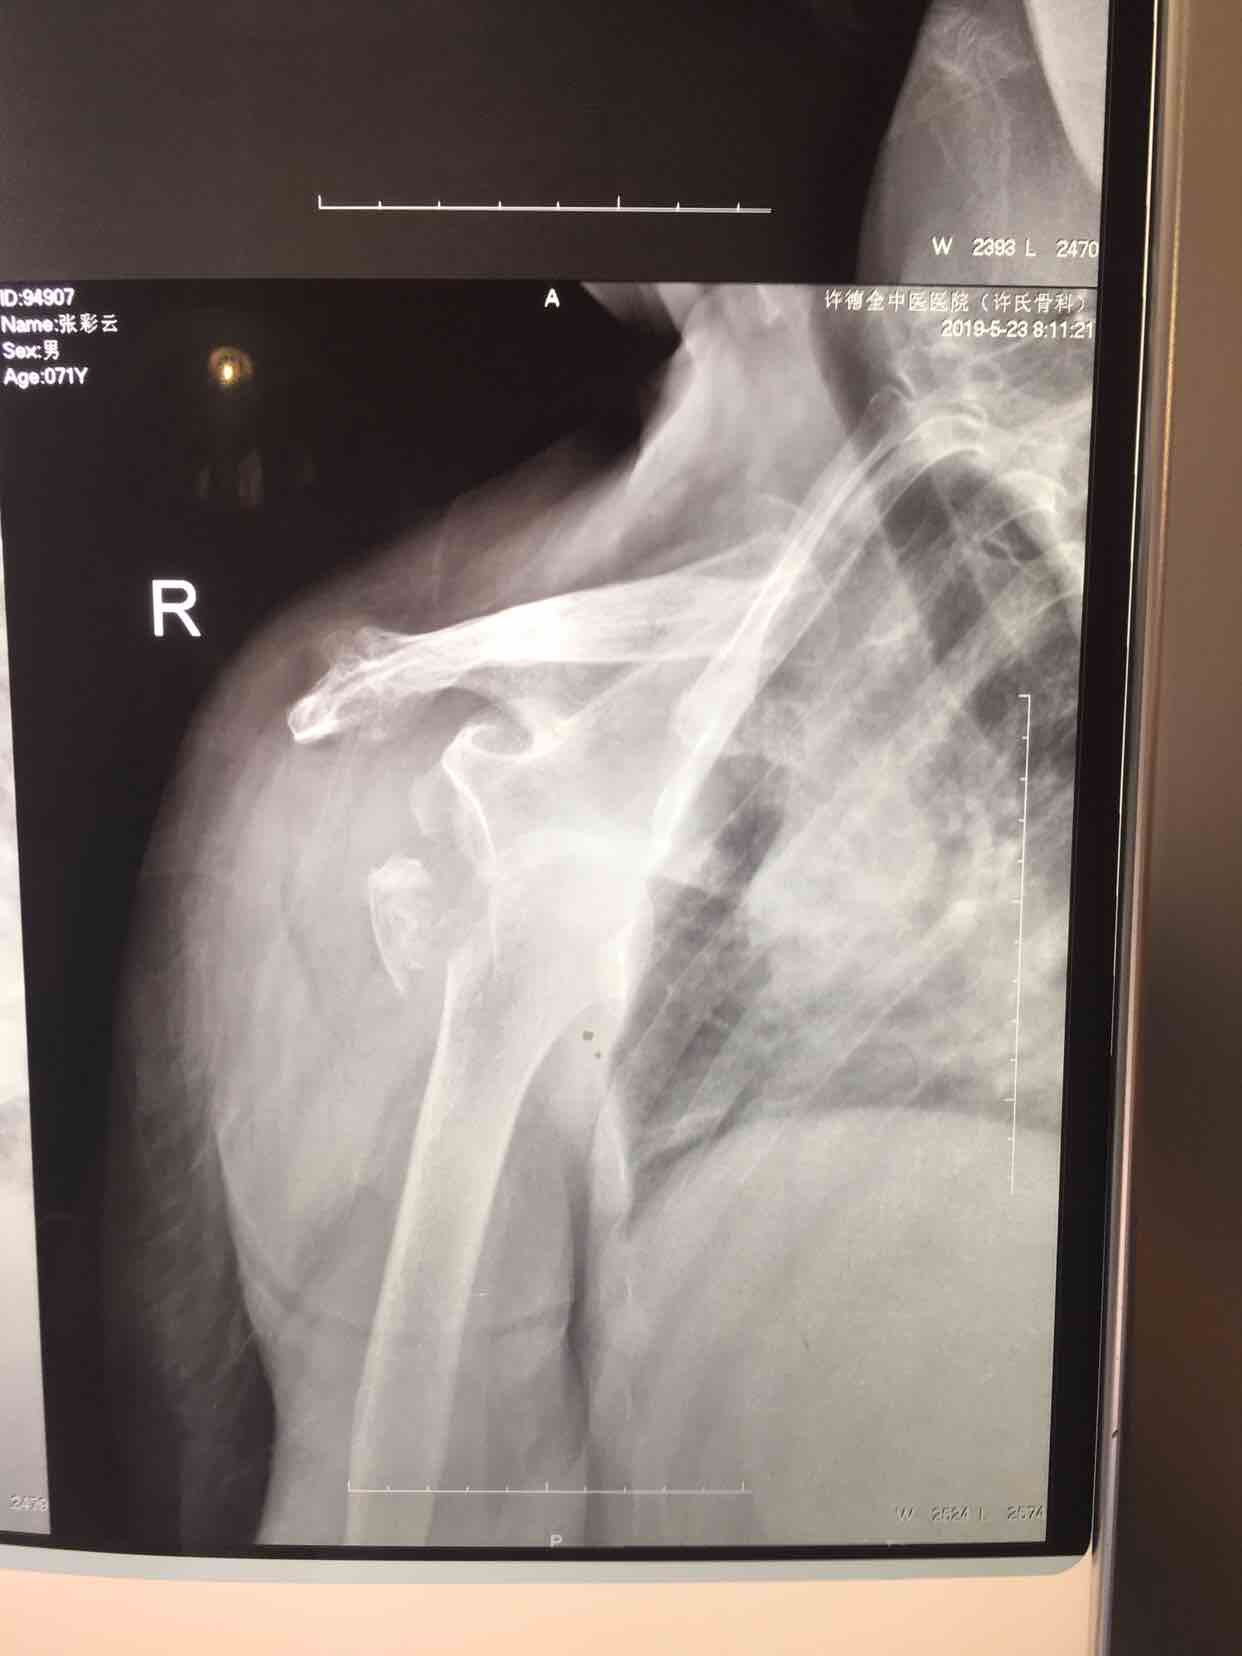

肩关节脱位并大结节骨折(切复内固定)

摔伤后右肩部肿痛,活动受限1天入院。既往患有冠心病数年,无特殊不良嗜好。

生命体征平稳,心肺腹未见异常。右肩部肿胀明显,局部皮色青紫淤瘢,皮温基本正常,搭肩试验阳性,关节盂空虚,肩关节活动受限,远端血运感觉正常。

诊断肩关节脱位并大结节骨折在臂丛麻醉下行切复内固定术,术后外展架固定,抗炎,消肿等处理。